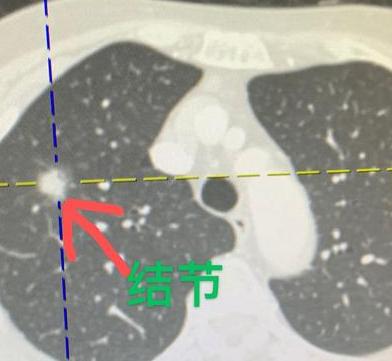

门诊来了一位74岁的阿婆,是她儿子陪着来的,看起来精神不太好,脸上挂满了忧虑。她告诉我,自己的妹妹十年前就是因为肺癌去世的。 正因为有这个家族史,老人家特别重视身体,每年都坚持做胸片检查,这些年的结果也一直正常。 直到今年,在医生的建议下,她把胸片换成了更清晰的胸部CT,这才发现肺里有个接近2cm的结节。 这个结节密度比较高,再加上她的家族史,确实需要警惕。看过片子后,我认为肺癌的可能性比较大。 其实关注过我的朋友都知道,我对肺结节一贯的态度是“不变不动”——只要结节不长大、不变化,通常建议定期观察,不轻易手术。 但仔细看了阿婆的片子后,我觉得这次的情况不太一样。我建议她先做个全身检查,如果没有转移迹象,手术切除会是更稳妥的选择。 后来的PET-CT结果显示,这是个孤立性肺结节,代谢偏高,但好在没有转移。和家人商量后,阿婆决定接受微创手术。我们在术中也做了快速病理化验,确诊是“肺浸润性腺癌”。 说实话,阿婆算是很幸运的。虽然结节不小,但还处在最早期的阶段,没有发生淋巴结转移。这种情况下的手术效果通常很好,术后五年生存率超过80%,而且大概率能够治愈,不需要再做放化疗。 这两天查房时,看到阿婆状态明显好了很多,心里的负担卸下了,脸上的笑容也多了起来。再过几天,她就可以顺利出院了。[玫瑰][谢谢]胸外科乔贵宾医生肺结节[超话]